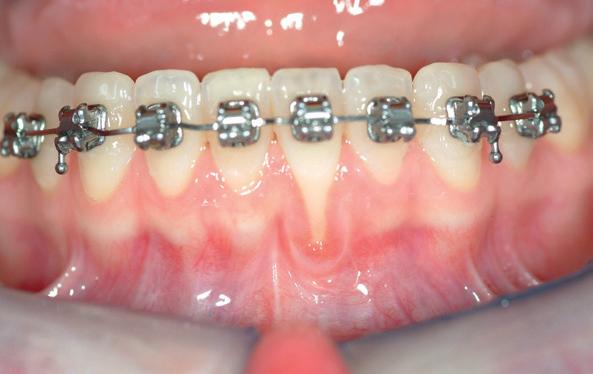

In de moderne orthodontie is het streven naar perfectie in esthetiek en functie vanzelfsprekender dan ooit. Met de opkomst van digitale behandelplannen, zelfligerende bracketsystemen en rechthoekige draden, is het manipuleren van tandstand in drie dimensies gemeengoed geworden. Een van de belangrijkste en tegelijk meest onderschatte krachten in deze driedimensionale tandverplaatsing is torque. Hoewel het nauwkeurig aanbrengen van torque cruciaal is voor een harmonieuze occlusie en esthetiek, schuilt hierin een reëel biologisch gevaar: het torque-gevaar.

Wat is torque?

Torque in orthodontie verwijst naar de gecontroleerde buiging van een wortel binnen het alveolaire bot, vaak gerealiseerd door een twist in een rechthoekige draad binnen een bracket. Deze beweging is essentieel voor het corrigeren van asstanden en het optimaliseren van de frontesthetiek. Echter, bij overmatige of ongecontroleerde toepassing kan torque leiden tot verplaatsing van wortels buiten de genetisch bepaalde botenvelop, met alveolaire botdehiscenties, gingivarecessies en zelfs aanhechtingsverlies als gevolg.

Retentie en het verborgen gevaar

De bonded retainer speelt een centrale rol in deze

2. Occlusale opname onderfront: standswijzigingen bij de 32 en de

31 door een geactiveerde retentie draad.

3. (Lokale) orthodontie leidt tot adequate standscorrectie met afname van de gingivarecessie bij de 31

problematiek. Hoewel bedoeld om stabiliteit te waarborgen, fungeert de retentiedraad bij loslating of vervorming geregeld als actieve orthodontische krachtbron. Elastic deflection of spanningsopbouw door parafunctie kan ongecontroleerde bewegingen veroorzaken waarbij tanden letterlijk “schommelen” rond een verstoorde as. Het gevolg: wortels die buccaal of linguaal buiten de botbegrenzing worden gedrukt met parodontale schade als gevolg.